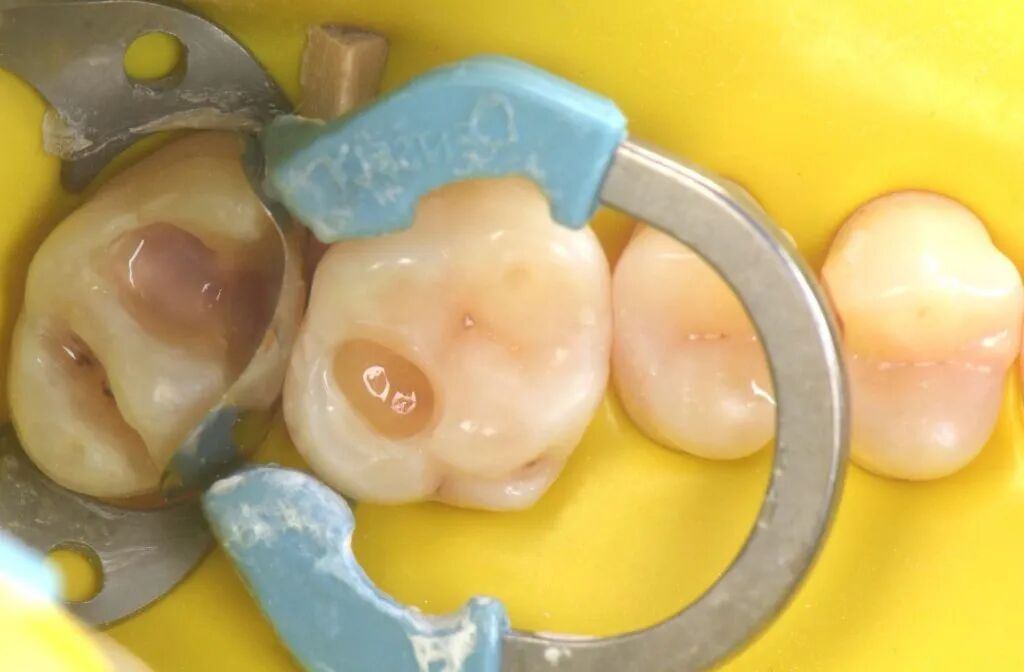

图1. 一位患者主诉左上后牙食物嵌塞咬合不适。左上象限(从第一前磨牙至第二磨牙)龋病情况如图。

图2. 在与患者讨论完治疗方法和风险后,清除龋损,恢复牙齿形态和功能是主要目标。

图3. 局部麻醉,橡皮障隔离,清理牙齿。

图4. 清除龋损后,29μm氧化铝喷砂清理洞壁、洞缘。

图5. 龋洞清理完成。准备酸蚀和黏结。

图11. 光固化垫底材料置于27窝洞最深处。

图12. 光固化20秒。

图13. 垫底后准备充填修复。